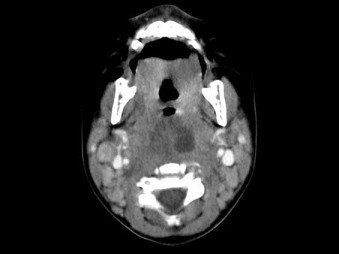

[多选题] 10个月大的婴儿,发热,曾患中耳炎,CT扫描如图所示,正确的描述或诊断是()A .咽后壁软组织肿胀B .其内密度不均C .颈椎骨质未见明显异常D .咽后壁脓肿E .咽后壁寒性脓肿

[多选题] 10个月大的婴儿,发热,曾患中耳炎,CT扫描如图所示,正确的描述或诊断是()A . 咽后壁软组织肿胀B . 其内密度不均C . 颈椎骨质未见明显异常D . 咽后壁脓肿E . 咽后壁寒性脓肿